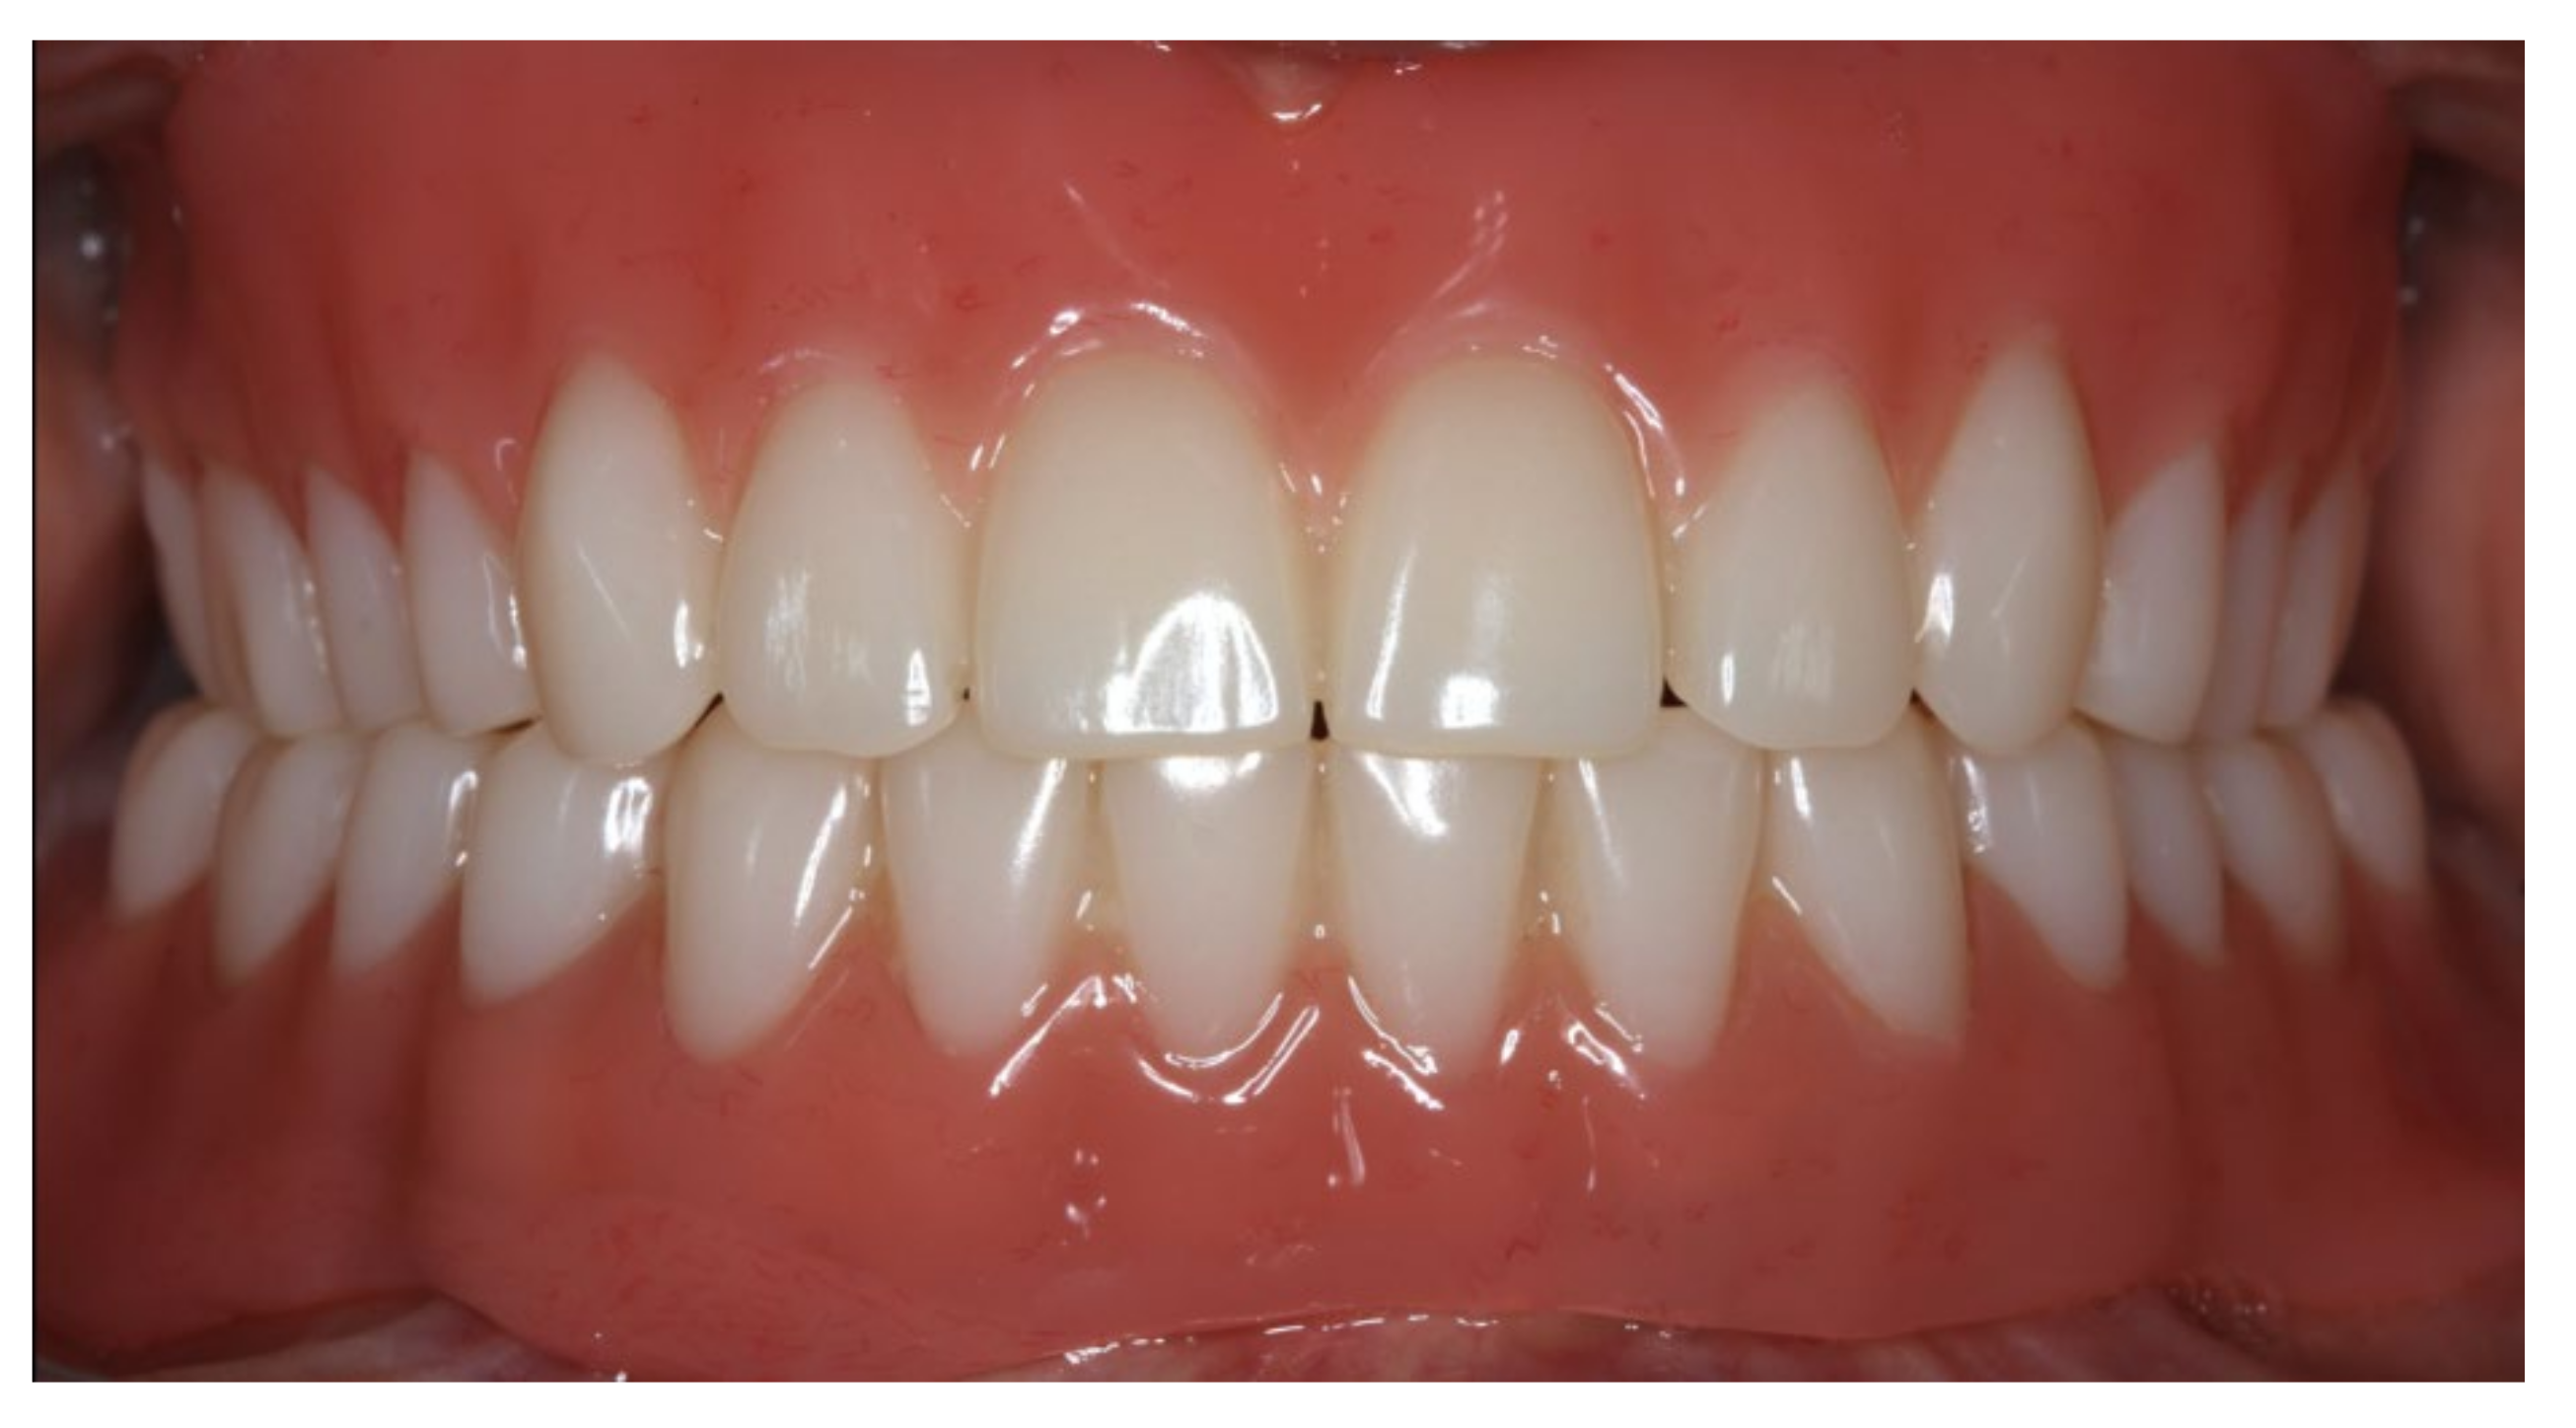

During the final appointment, the Locator abutments were tightened with torque (0.35 Nm) and the dentures were inserted. The attachment patrices were equipped with inserts producing intermediate retention (green). Occlusion, extension, retention, and aesthetics were carefully controlled and adjusted where appropriate (Figure 19, Figure 20 and Figure 21). Both dentures featured excellent retention and fit. Finally, the patient was instructed regarding insertion, removal, and maintenance of the dentures. After one week, the patient was satisfied with the new prostheses and no complications were reported or identified.

Figure 21.

Anterior view of the inserted dentures in centric occlusion.